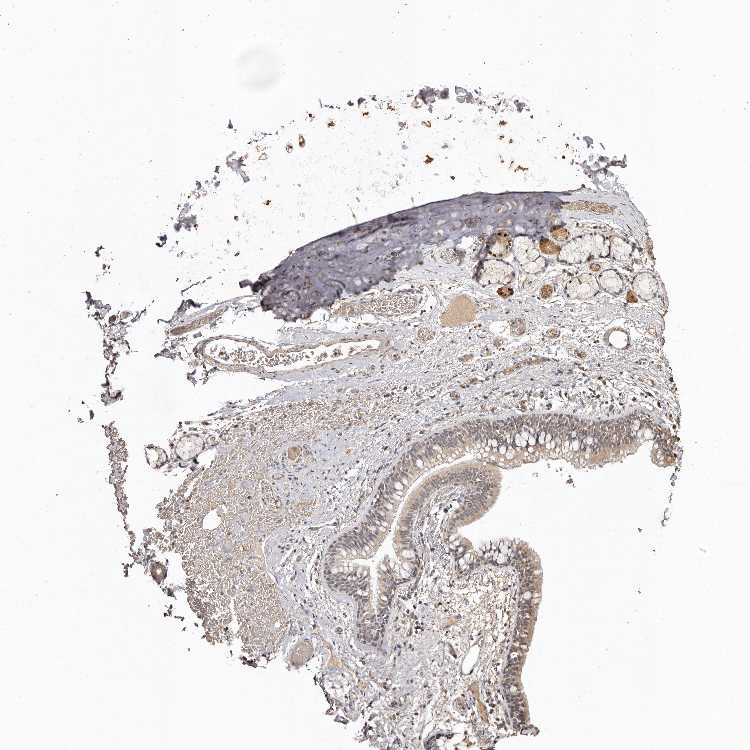

SOFT TISSUE 1 - Antibody stainingi

Antibody staining in the annotated cell types in the current human tissue is reported as not detected, low, medium, or high, based on conventional immunohistochemistry profiling in selected tissues. This score is based on the combination of the staining intensity and fraction of stained cells.

Each image is clickable and will lead to virtual microscopy that enables deeper exploration of all samples and also displays staining intensity scores, fraction scores and subcellular localization as well as patient and tissue information for each sample.

Antibody HPA027499Antibody HPA027511

Chondrocytes MediumNot detected

Fibroblasts LowNot detected

Peripheral nerve MediumMedium